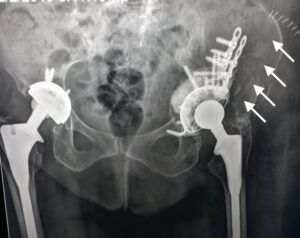

- Ακτινογραφία που εκ πρώτης όψεως δείχνει να μην έχει σοβαρό πρόβλημα, όμως έχει τεράστιο περιπροθετικό κάταγμα της κοτύλης. Έχει αποκολληθεί το εμφύτευμα από τη θέση του και έχει αποσπασθεί μαζί με ολόκληρο το οστικό οπίσθιο τοίχωμα της κοτύλης

- H τελική ακτινογραφία με ευμεγέθες εμφύτευμα τανταλίου (buttress augment) , άμεση κινητοποίηση ασθενούς με πλήρη αποκατάσταση!!